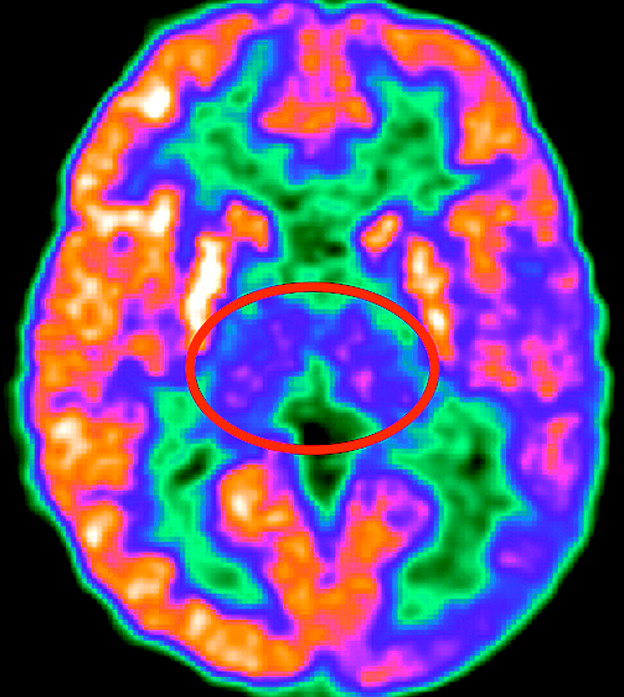

Study recruitment will be ongoing for the next three and a half to four years, providing funding continues. The study, which will last about 26 weeks, involves an initial phone screening to determine eligibility, lab visits at Vanderbilt, intensive reading interventions, MRI scans and, for some participants, an investigational study medication. Participants will be compensated up to $1,050, in addition to travel reimbursement for families living outside Middle Tennessee.

The goal of the study is to determine the best ways in which people with neurofibromatosis Type 1 who struggle with reading can learn to become good readers. The principal investigator of the study is Laurie Cutting, Patricia and Rodes Hart Professor of Special Education at Peabody College, professor of pediatrics in the Vanderbilt School of Medicine, and associate director of the Vanderbilt Kennedy Center.